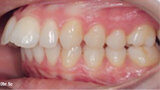

Distalizace horních molárů pomocí alignerů a cyklických sil